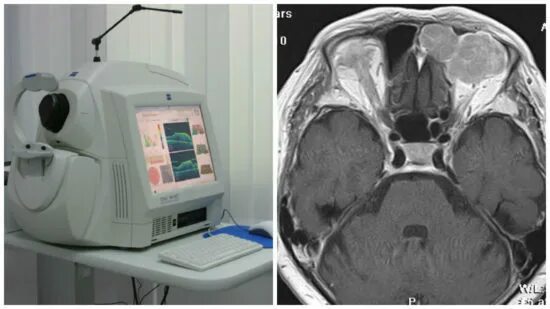

Мрт орбит и зрительных нервов